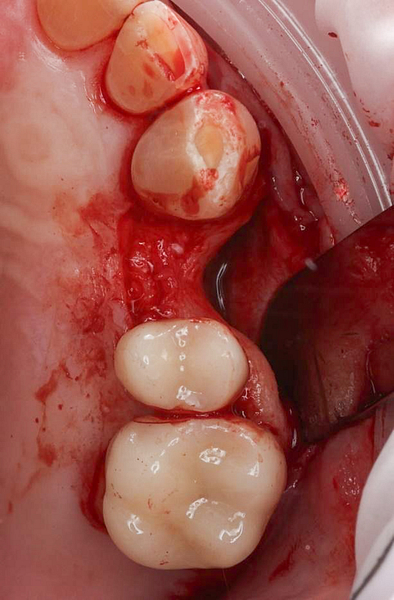

Upon examination by his previous dentist, a vertical root fracture was diagnosed, necessitating a surgical extraction. The procedure, which involved removing the buccal cortical bone, left the patient with a bony defect in the area of the extracted tooth.

Surgical Phase

The surgical phase of the implant treatment is a critical step in ensuring the success and longevity of the final restoration.

I utilized 3Shape Implant Studio, a module within the 3shape Unite Platform, to plan and execute the surgical procedure.

Pre-surgical planning began with acquiring high-quality diagnostic data, including TRIOS intraoral scans and CBCT imaging. The data was imported into 3Shape Implant Studio, where I designed a virtual crown for tooth 24 and planned the precise positioning of the implant, considering critical factors such as sinus proximity, adjacent roots, bone density, and the location of the bony defect.

A custom surgical guide was designed and 3D printed, incorporating all the critical information from the virtual planning. The implant surgery was performed under local anesthesia, with the surgical guide firmly in place to ensure accurate implant placement. Bone grafting was performed to address the bony defect and promote optimal healing.

The Osstem OneGuide kit is used with a fully guided osteotomy and implant placement.

Osstem TSIII D4 x H10mm implant on NoMount driver.